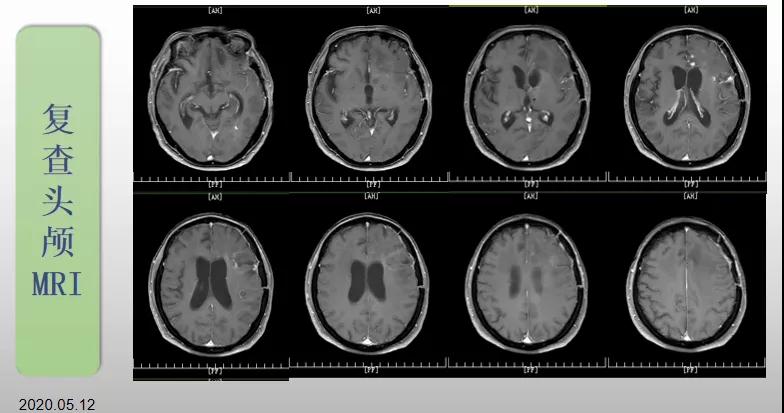

綜合治療 電場治療助70歲患者回歸正常生活

70歲的郝女士去年曾在外院查出“左額島葉”膠質(zhì)母細(xì)胞瘤(WHO Ⅳ級(jí)),并做了左側(cè)額島葉占位性病變切除術(shù)。術(shù)后進(jìn)行了同步放化療。由于治療條件有限,郝女士慕名來到我院就診。賀世明主任率領(lǐng)醫(yī)護(hù)團(tuán)隊(duì)立即為郝女士進(jìn)行了全面的檢查,決定為其進(jìn)行綜合治療 電場治療。經(jīng)過三個(gè)多月的綜合治療,患者復(fù)查頭顱MRI病變較前明顯縮小。出院時(shí),郝女士神志清醒,睡眠飲食正常,說話很流利?!拔沂翘芍M(jìn)來的,現(xiàn)在不用人攙扶,自己就可以走出病房了?!焙屡坷t(yī)護(hù)人員的手說。